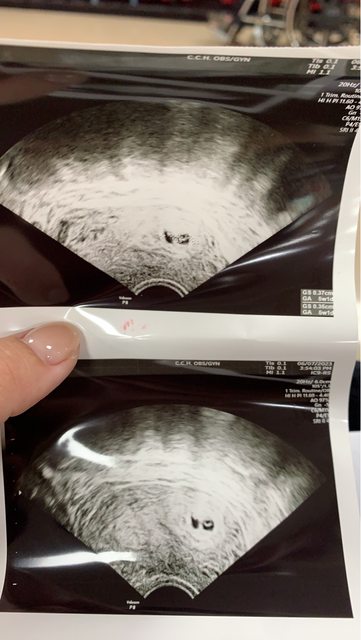

雖然還很早期也是第二胎了 但還是很焦慮想抒發一下 以下是心情流水帳 媽媽本人的爸爸(外公)就是雙胞胎 所以一直很期待有機會懷上雙胞胎 大寶快2歲的時候小寶寶來報到了 因為自己有在記錄經期所以一晚來就去驗孕了自己推算大概5W 驗孕前一天還因為整理家裡從很高的地方摔下來... 知道這麼早可能還沒有心跳也不急著去產檢 結果驗孕後4天突然開始有些微出血 (距離摔倒5天了應該不是原因) 不會滴下來的程度但上完廁所一擦衛生紙都是鮮紅色+分泌物 6/7產檢時照陰超 一看到畫面很明顯兩個胎囊 之後醫生驚喜地問你們家裡有雙胞胎基因嗎? 我馬上就泛淚了(第一胎都沒這麼感動) 但是還沒有心跳 打了50mg的油針跟拿了小白球安胎 隔天好很多 只剩下褐色分泌物 結果6/9突然開始大出血 一早起來衛生紙一擦是鮮紅的 這時還沒到非常多 想說趕快在上班前去醫院檢查 結果車子一停好下車瞬間感覺一股熱流...... 趁等候看診的時候去廁所已經是整片護墊鮮紅連內褲都是... 進診間照陰超的時候血也是滴滴答答流不停 當下心情已經整個沉下去 還問醫生是不是一個沒了 (因為超音波我只看到一個) 醫生說兩個都還在 一個有心跳了 子宮裡有血塊 目前只能打安胎 吃小白球跟止血藥 3個月前都可能是自然淘汰 這些我都知道... 但還是很不安 這次打了125mg的普寶胎說可以撐一個禮拜 打完針想去廁所我突然感覺腳濕濕的 血竟然沿著腳整個流出來 連走廊地板都是 完全是比mc來得時候量還多好幾倍了... 但醫生說現在能做的只有這些 我只能回家休息一直爬文做好心理建設 附上5w超音波照片 一看很明顯就是兩個胎囊 這樣就是異卵了嗎? 希望一切順利~ https://i.imgur.com/cpVQXNs.jpg